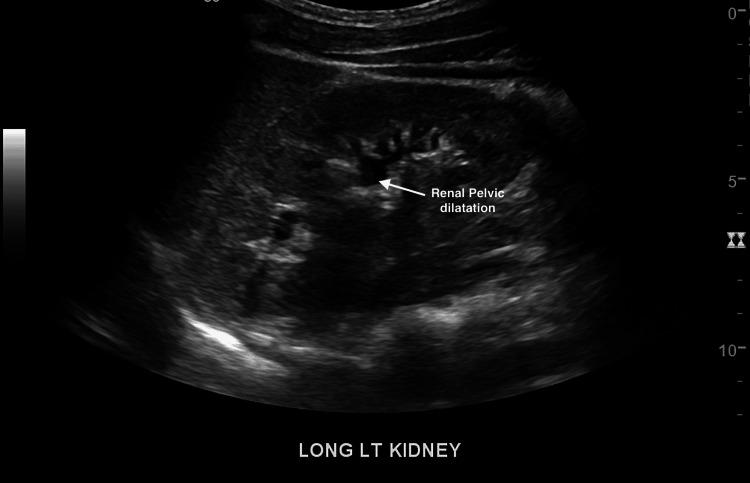

Celiac artery compression syndrome is not frequent in the pediatric population. The syndrome may entail long-standing abdominal pain, recurrent vomiting, bloating, weight loss, and an abdominal bruit, which in the case of our patient, was an incidental finding. Notably, patients may be asymptomatic.  Our patient is a 16-year-old male who presented with concerns about multiple, non-tender chest lymph nodes lasting for two weeks. He had also lost 80 lbs. over one year. On examination, however, an abdominal bruit was discovered, and a diagnostic workup was significant for celiac artery compression following a magnetic resonance angiography of the abdomen. Due to his significant weight loss and mediastinal lymphadenopathy, a chest computed tomography (CT) scan was done to rule out malignancy. The chest CT scan was reported as normal. Additionally, a renal duplex ultrasound was done to rule out renal artery stenosis, considering he had presented with elevated blood pressure; this was also unremarkable. Although this patient had a history of marijuana use, his assessment did not show marked dependence. Substance abuse and atherosclerotic vascular disease can be predisposing factors for celiac artery compression syndrome in older individuals. However, compression of the celiac trunk by the median arcuate ligament is a congenital anomaly more appreciated in younger age groups. The patient was referred to vascular surgery for possible median arcuate ligament release.

腹腔干压迫综合征在儿科人群中并不常见。该综合征可能导致长期腹痛、反复呕吐、腹胀、体重减轻以及腹部血管杂音,在我们的患者中,腹部血管杂音是偶然发现的。值得注意的是,患者可能没有症状。我们的患者是一名16岁男性,因持续两周的多个无痛性胸部淋巴结问题前来就诊。他在一年多的时间里还减重了80磅。然而,在检查时发现了腹部血管杂音,腹部磁共振血管造影显示腹腔干压迫,诊断检查结果显著。由于他体重显著减轻且有纵隔淋巴结肿大,进行了胸部计算机断层扫描(CT)以排除恶性肿瘤。胸部CT扫描报告正常。此外,考虑到他曾出现血压升高,进行了肾脏双功超声检查以排除肾动脉狭窄,结果也无异常。尽管该患者有使用大麻的病史,但他的评估未显示出明显的依赖。药物滥用和动脉粥样硬化性血管疾病可能是老年个体腹腔干压迫综合征的易感因素。然而,正中弓状韧带对腹腔干的压迫是一种在年轻人群中更易发现的先天性异常。该患者被转诊至血管外科,考虑可能进行正中弓状韧带松解术。